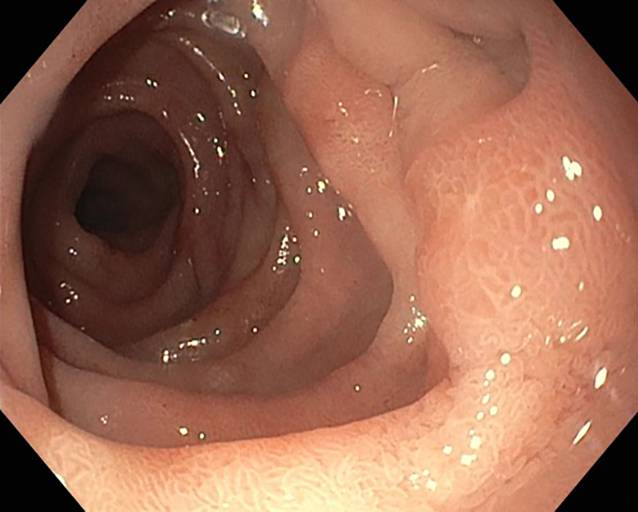

After 5 days, the patient presented on an emergency basis due to the clinical suspicion of a misplaced nephrostomy catheter. Biliary secretions were draining out of the catheter. There was no pain or fever or macrohematuria. Laboratory chemistry tests did not show any elevated infection parameters. On ultrasound, grade 2–3 hydronephrosis was found in the right renal pelvicalyceal system, and the left kidney was unobstructed. A plain X‑ray in one plane showed the nephrostomy from the right side with the tip projecting into the renal pelvis at the level of the right transverse process of L1 (Fig. 1).

Fig. 1

Nephrostomy catheter in place, plain X‑ray at the time of admission